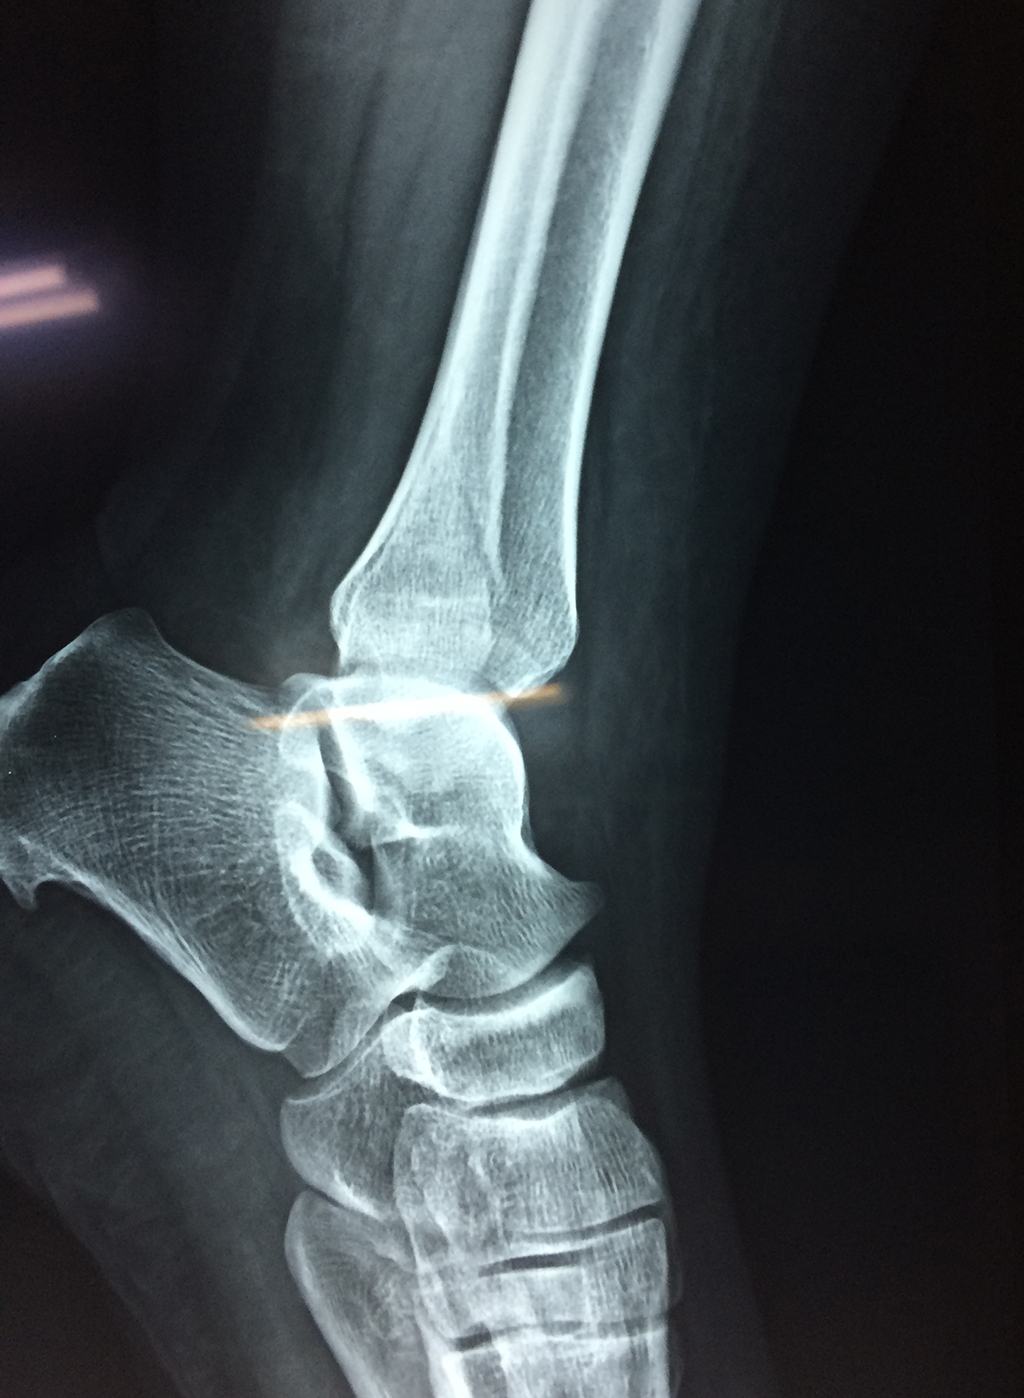

Una fractura de tobillo es la rotura de uno o más de los huesos del tobillo. Estas fracturas pueden ser:

- Parciales (el hueso está sólo parcialmente fisurado, no del todo).

- Completas (el hueso está perforado y está en 2 partes).

- Producirse en uno o ambos lados del tobillo.

Algunas fracturas de tobillo pueden requerir cirugía si:

- Los extremos de los huesos están desalineados entre sí (desplazados).

- La fractura se extiende hasta la articulación del tobillo (fractura intra-articular).

Cuando se necesita cirugía, es probable que esta implique el uso de clavijas de metal, tornillos o placas para sostener los huesos en su lugar mientras la fractura se consolida. Los elementos de soporte pueden ser temporales o permanentes.